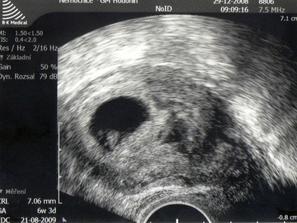

22.12.2008 Tak to vypadá,že mě čeká zase revize.V děloze jen dutinka.Uvidíme co odběry a kontrolní ultrazvuk.Ale mám takové tušení,že je to zase špatně.hCG 14520j.Něco se tam děje.Mám přijít na další ultrazvuk 29.12.******************************************

Tak 29.12. je pro mě šťastný den.Na ultrazvuku potvrzeno těhotenství.Mimísek byl krásně vidět a dokonce už tlouklo i srdičko.Dle ultrazkuku jsem 6+3.Takže ovulka byla později.Obrečela jsem to.Tak snad už bude vše OK.Děkuji všem,kteří mě drželi pěsti.**************************2.1.2009 začalo pobolívat bříško,tak jsem zůstala v nemocnici.Mimi se má k světu.5.12. jsem byla na ultrazvuku jsme 8 tt a máme 1,25 cm.To je macek,že?6.1.2009 jsem byla propuštěná z nemocnice.Konečně doma.Máme neschopenku a prý už na celé těhu.Na další kontrolu jdu 20.1. v 9 hodin.Už teď se bojím,aby bylo vše vpořádku.Jsem asi blázen.*************************************************